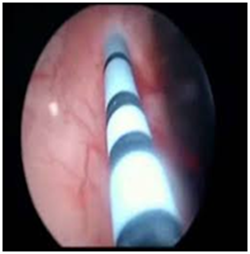

Abdomino-pelvic ultrasound scan revealed an intrauterine viable gestation of 13 weeks with 5 days old as shown in Figure 1A, there was also dilatation of the pelvicalyceal system involving the proximal part of left ureter and presence of 2 calculi within the left renal pelvis, the larger one measured 1.6cm in size as shown in Figure 1B and the right kidney was normal. Serum electrolytes, Urea and Creatinine including urinalysis, urine culture and full blood count were normal. She was then planned and had urethrocystoscopy and Double J stenting of the left ureter under general anaesthesia as shown in Figure 2A. Cystoscopic findings were minimal resistance while stenting the left ureter, which was ultimately, overcame, otherwise normal bladder mucosa and ureteric orifices and no stones within the bladder. Postoperative condition was satisfactory and symptoms subsided. She was later discharged home on oral antibiotics. Since then, she has been regular with her follow up and has been doing well until when she was re-admitted with an assessment of anemia in pregnancy secondary to Malaria and Urinary Tract Infection (UTI) at 32nd week gestation. She responded well to antibiotics and antimalarial, and also had blood transfusion. The serial electrolytes urea and creatinine remained normal. The pregnancy was monitored till term and had spontaneous delivery of normal female neonate weighing 3kg. Patient was re-evaluated in the first week of puerperium, the findings from the repeated abdominal ultrasound scan and KUB were 2 left renal calculi, and one of them has already enlarged to a bigger size of 2.5cm in its widest dimension and presence of intact left ureteric double J stent, otherwise no soft tissue or bony abnormalities seen. She later had left Nephrolithotomy and extraction of double J stent. Intra-operative findings were ‘’stag horn calculus’’ with another small calculus in the left renal pelvis as shown in Figure 2 (B & C). Post-operative condition was satisfactory and was later discharged home. The metabolic evaluation and stone analysis revealed calcium oxalate and calcium phosphate and she was counseled on dietary calcium.

Figure 2(A) Cystoscopy and ureteral DJ stenting.